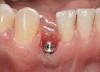

Fig 33. Excessive facial angulation of the implant placement shown with an abutment driver in the access screw hole.

Fig 34. A surgical cover screw was placed in an attempt to decoronate the implant and gain soft-tissue coverage in situ.

The following case report provides an example of this case scenario: A 24-year-old white male presented with congenitally missing tooth No. 26 restored with a single-tooth cement-retained implant restoration. The implant was placed excessively to the facial aspect of the edentulous site and too shallow, and the periodontal phenotype was thin scalloped (Figure 32). In an effort to mimic the lost midfacial soft tissues, pink ceramics were used as a cosmetic facade. Even though the restoration was not in the esthetic zone, the patient was highly displeased with the esthetic outcome and sought remediation.

The crown and screw-retained custom abutment were removed, and a surgical cover screw was placed into the implant, thereby allowing spontaneous gingival augmentation in situ (Figure 33 and Figure 34). Note that the lingual aspect of the implant site was significantly more coronal than the labial aspect, which was positive because the defect would be limited to a facial–lingual defect. A fixed RBR bridge was cemented on the adjacent teeth and used as a tooth-supported transitional provisional restoration (Figure 35). A few weeks were allotted to let the soft tissue heal and migrate around the cover screw (Figure 36) to see if there would be complete coverage, thereby allowing a soft-tissue augmentation procedure to be performed with primary flap closure as in clinical scenario No. 2. The major obstacle in achieving a positive tissue response was that the implant depth was also deficient because the implant–abutment connection was at the level of the free gingival margin. It was decided that the best treatment option would be to remove the implant. A high-powered reverse-torque device (Fixture Remover Kit, NeoBiotech, www.neobiotechus.com) was used to remove the implant atraumatically (Figure 38 through Figure 41). The implant socket was allowed to heal for several months not unlike an extracted tooth (Figure 42). A new implant was placed in a better position from both a restorative and esthetic perspective (Figure 43), and after a few months of healing, a new crown was made (Figure 44). A satisfactory functional and esthetic result was achieved (Figure 45 and Figure 46) without employing pink porcelain.